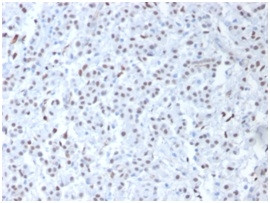

Wilm's Tumor 1 (WT1) (Wilm's Tumor and Mesothelial Marker) Polyclonal Antibody